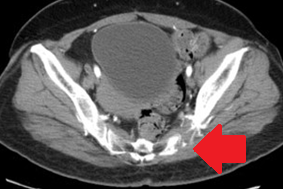

Αξονική τομογραφία κοιλίας. Φεβρουάριος 2017. Εμφανίζεται η υποτροπή του οπισθοπεριτοναϊκού αγγειοσαρκώματος (κόκκινα βέλη)